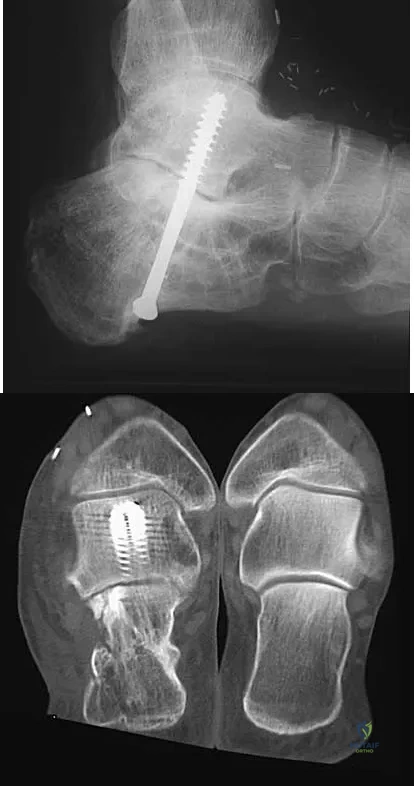

A 45-year-old man has persistent hindfoot pain that is aggravated by weight-bearing activities. History reveals that he sustained a calcaneus fracture 2 years ago, and he underwent a subtalar fusion 1 year ago. Examination reveals tenderness in the sinus tarsi and across the transverse tarsal joint. A plain radiograph and a CT scan are shown in Figures 24a and 24b. A technetium Tc 99m bone scan reveals uptake at the subtalar joint and at the transverse tarsal joints. Management should now consist of

Explanation